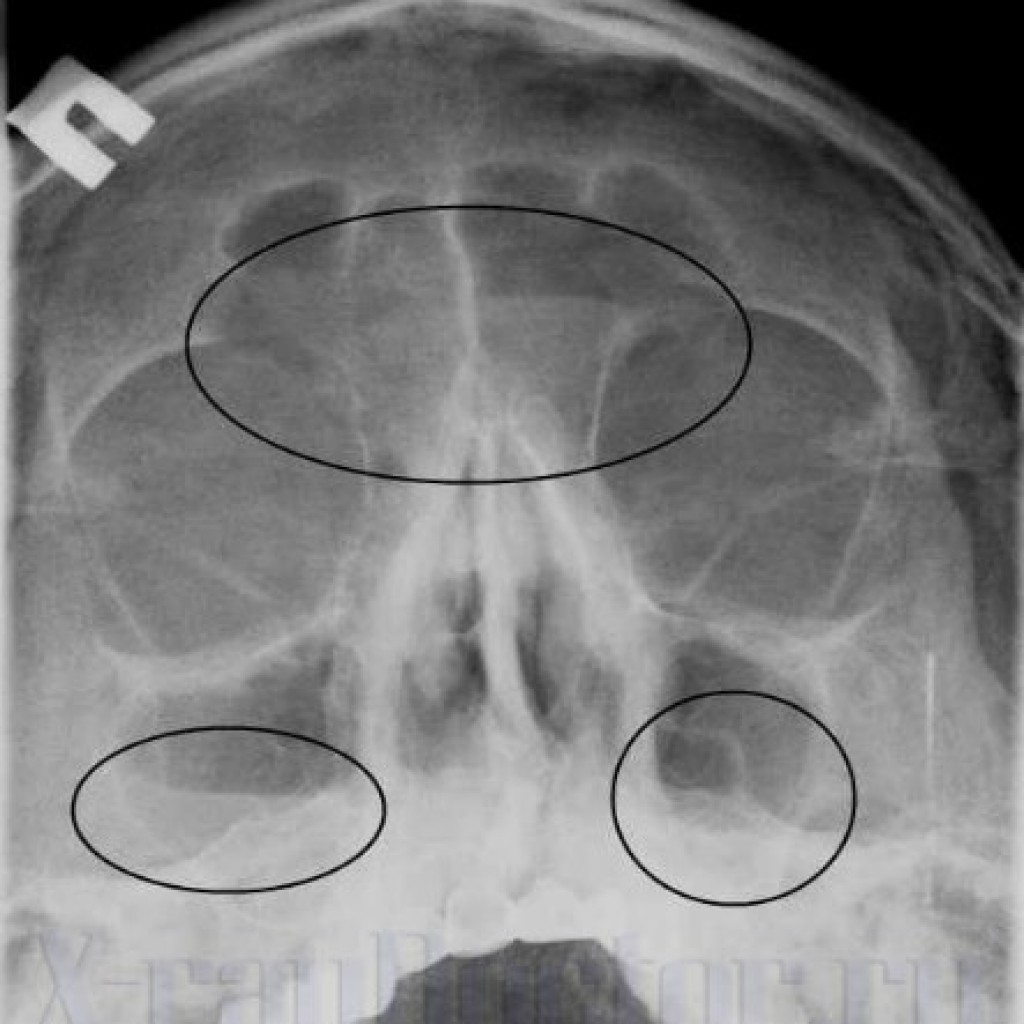

КТ-снимки хронического этмоидита: подробная визуализация

Раздел: Фотодневник открытий